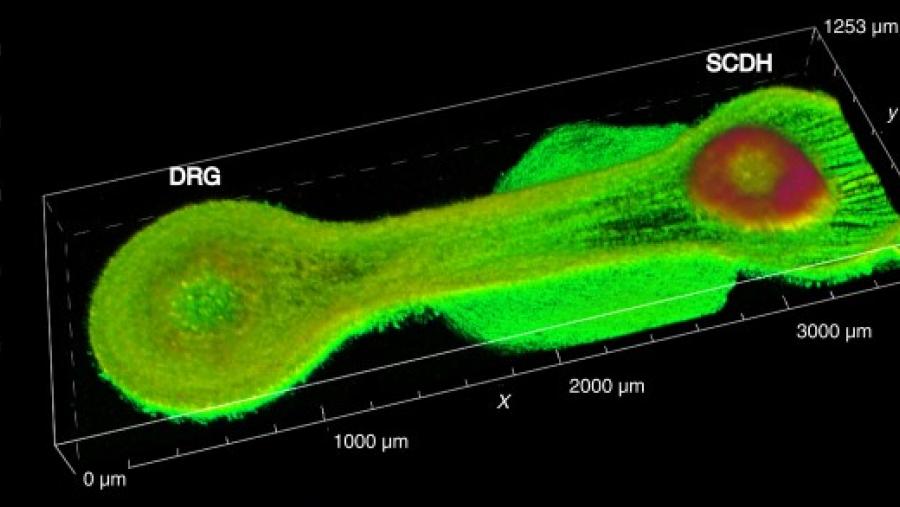

Image

A molecular inventory of pain-sensing nerve cells may lead to more targeted therapies

Published: November 7, 2023

Topics:

Novel Targets

Image

Tissue chip-based model screens potential pain medications faster

Published: December 10, 2021

Topics:

New Drugs/Screening Tools